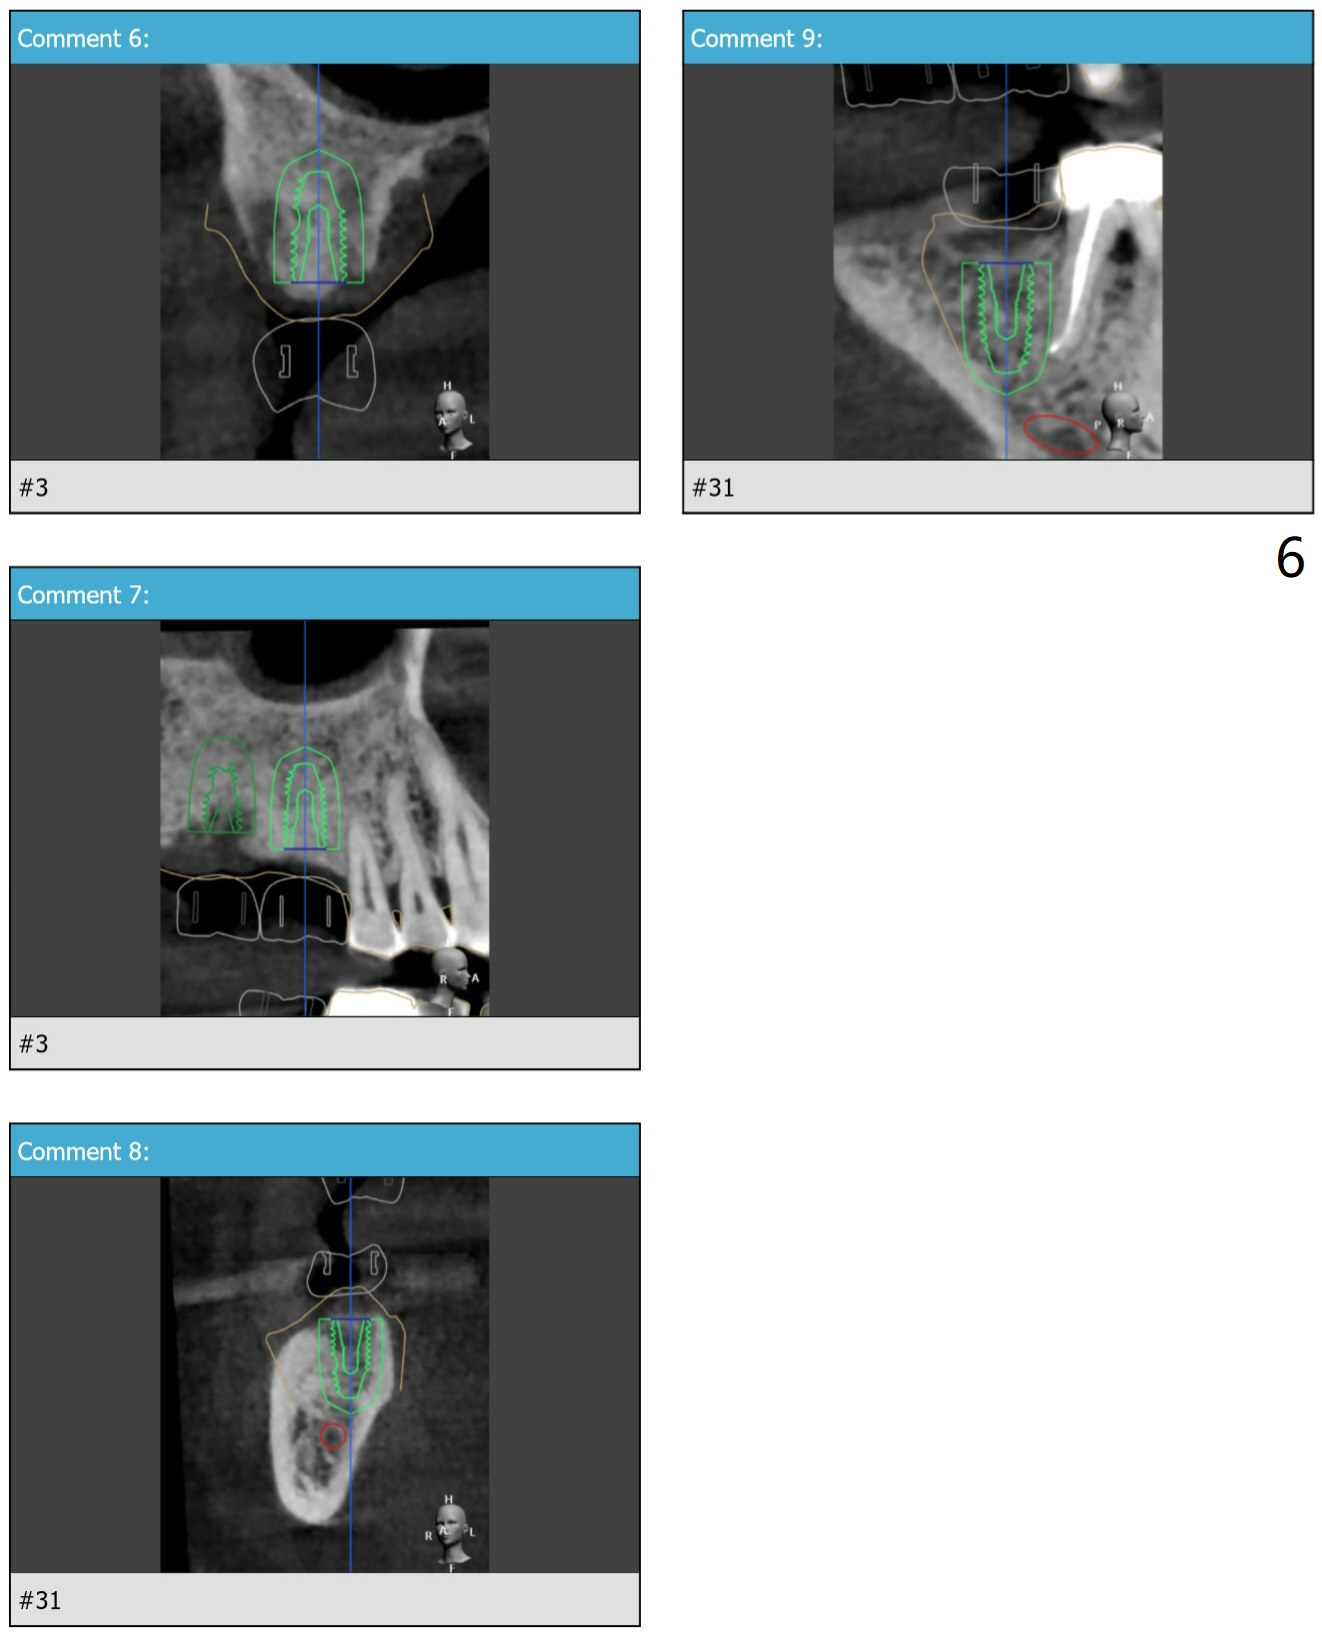

Three Implants On the Right M

A 65-year-old man agrees to have #2,3,31 implants placed following those of #14,15 (Fig.1).